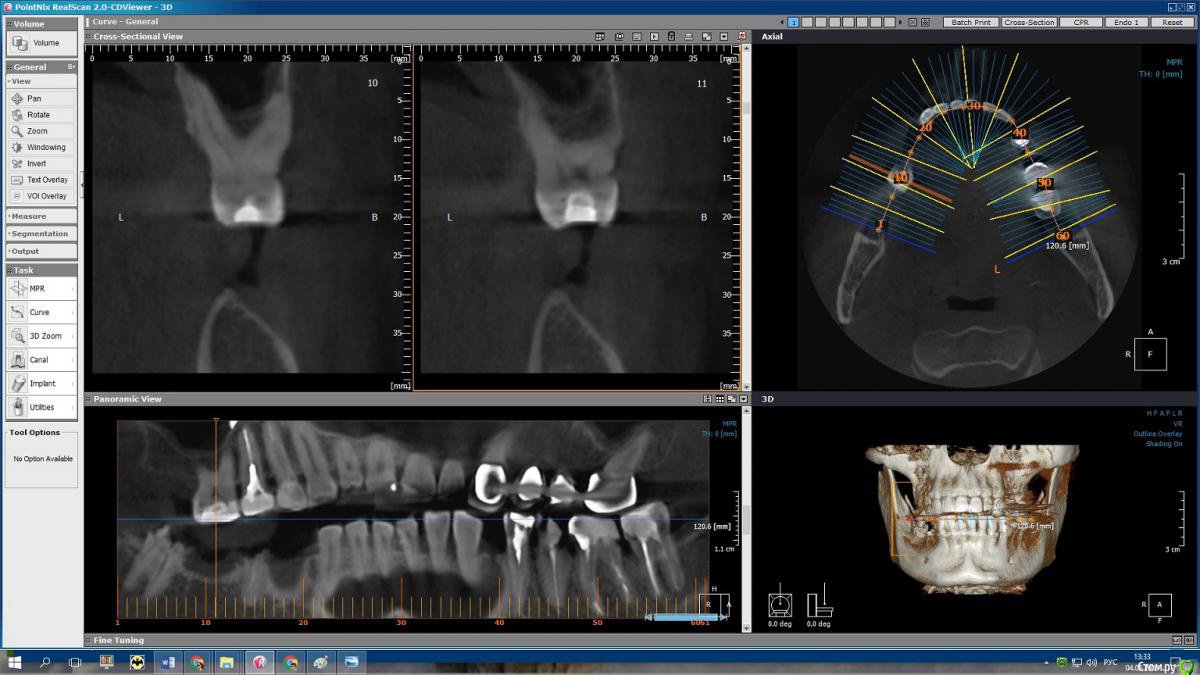

msa Опубликовано 27 февраля, 2019 Поделиться Опубликовано 27 февраля, 2019 Здравствуйте, уважаемые доктора!Прошу совета в выборе оптимального плана лечения и восстановления зубного ряда.Слева вверху (2.3-2.6) мост м/к с 1998 г(со слезами обточила здоровый красивый клык).Справа внизу был мост м/к 2006г на 4.4-4.7 (опорный моляр 4.7 + штифт в 4.5, конструкция была не очень, т.к. не отдала обтачивать под коронку клык 4.3) Через 7 лет мост слетел… От слова совсем.В н/вр пытаюсь понять, нужно ли бороться за премоляр 3.5 Или однозначно удалять? Можно ли сохранить 3.6 с помощью культевой вкладки?Какие варианты оптимального замещения низа справа 4.4-4.7? Корни пока не удаляю. Жизнеспособен ли верх 1.4-1.6? (пломбам больше 20 лет) Скриншоты из КТ от 25.02.19 ОПТГ не делалаСпасибо!С уважением, Марина Ссылка на комментарий

msa Опубликовано 27 февраля, 2019 Автор Поделиться Опубликовано 27 февраля, 2019 (изменено) Нужна ОПТГ или панорамный срез из КТ Получилось немного кривоватокрупно Изменено 27 февраля, 2019 пользователем msa Ссылка на комментарий

msa Опубликовано 1 марта, 2019 Автор Поделиться Опубликовано 1 марта, 2019 Результат очного осмотра:-верх справа/ 1.4, 1.5, 1.6 лечить, вкладки, коронки (если выдержат)-низ справа/ 2 импланта в области 4.5 и 4.7 ( кость нормальная) Очень расстроил низ слева / 3.5 -удаление, 3.6 -удаление/ имплантыНеужели однозначно удалять все? Please help me! Ссылка на комментарий

kramer Опубликовано 1 марта, 2019 Поделиться Опубликовано 1 марта, 2019 По таким срезам сложно сказать, к тому же без осмотра. Раз врач сказал... Ссылка на комментарий

suballex Опубликовано 4 марта, 2019 Поделиться Опубликовано 4 марта, 2019 Ревизия 14,15 терапевтом.Ревизия 37,36,35,34 терапевтом. По результатам ревизии - решение о сохранении зубов. Не по результатам КТ. Врачи лечат не рентген, а пациента. Терапевт убирает все реставрации и рецидивы, оценивает объем сохраненных тканей.47,45 удалитьИмпланты 46,44Если после ревизии все зубы сохраняются:- Коронки на свои зубы 14,15,37,36,35,34- Мостовидный протез на импланты 46-44 23,26 предоставленной информации не достаточно. А ссылка ваша глючит. 1 Ссылка на комментарий